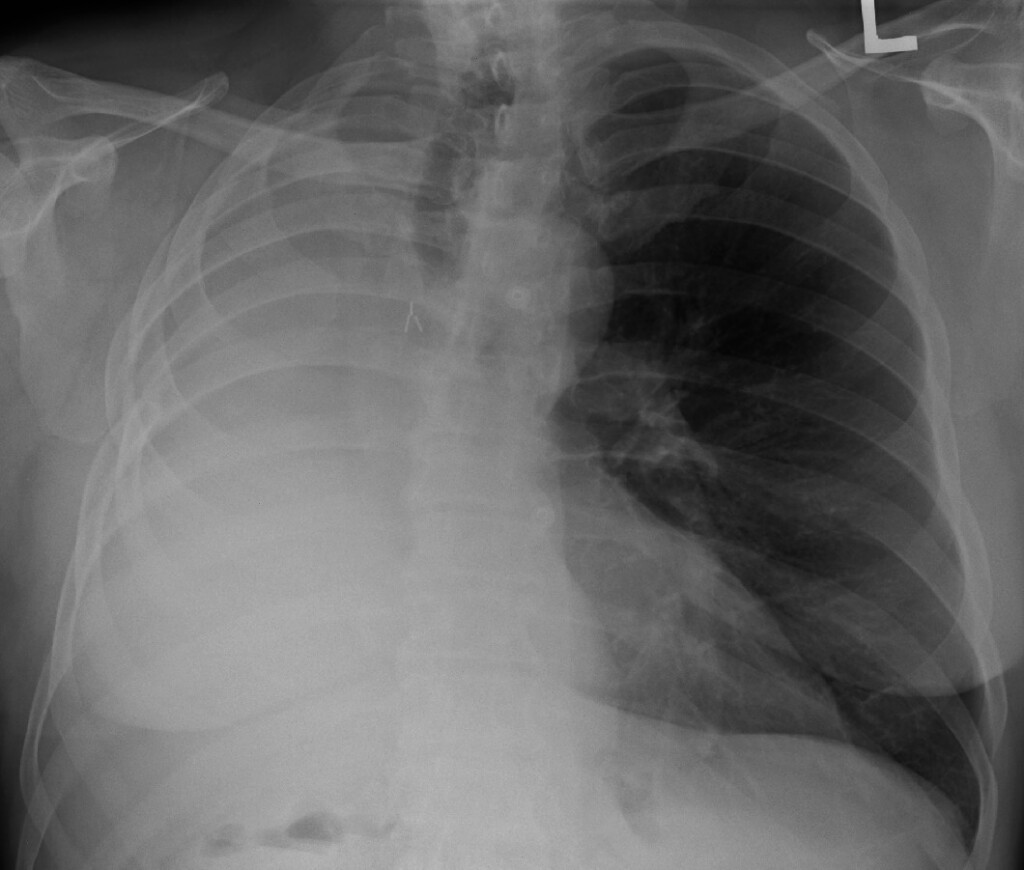

How Long Can You Live with a Collapsed Lung(Pneumothorax) . While most people with two lungs expect people with one lung to be winded all the time, the surprising fact is that the remaining lung expands to replace the space in the chest. Cancer or other health problems could lead you and your doctor to decide to remove one of your lungs